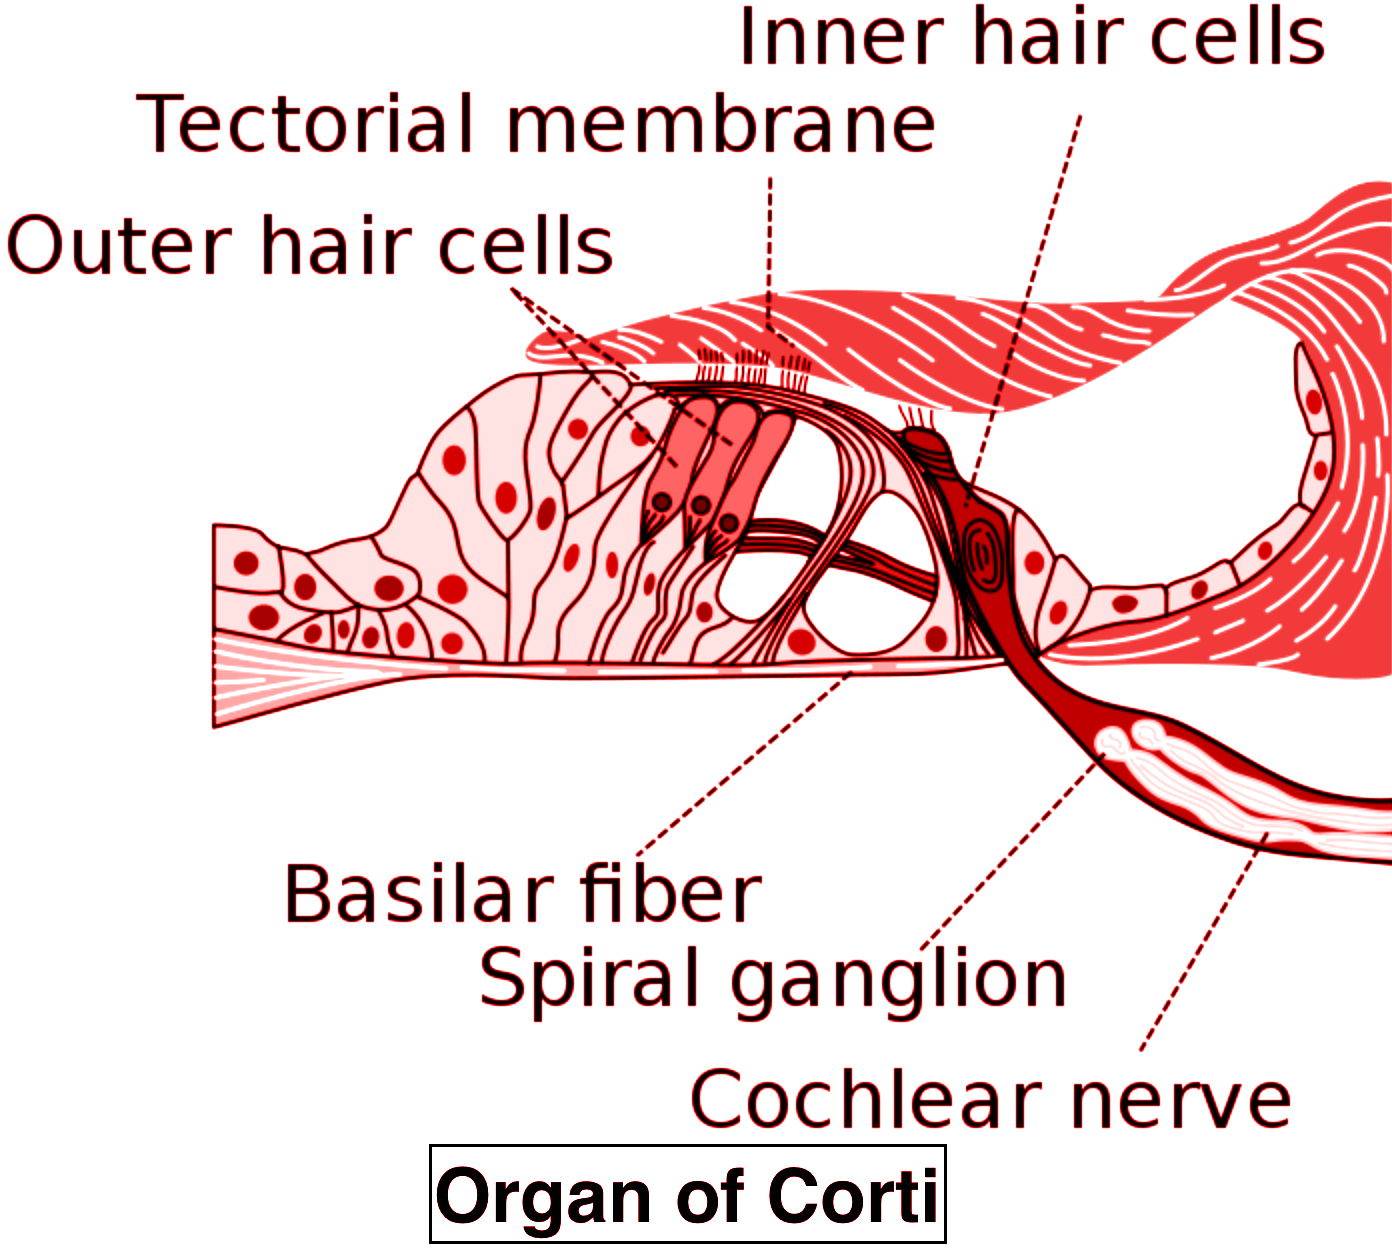

The tectorial membrane is found in the A Eye of frog class 11 biology CBSE

CBSE Papers, Questions, Answers, MCQ …: CBSE Class 10 – Physics …

vision and the eye (lesson 1063) – TQA explorer